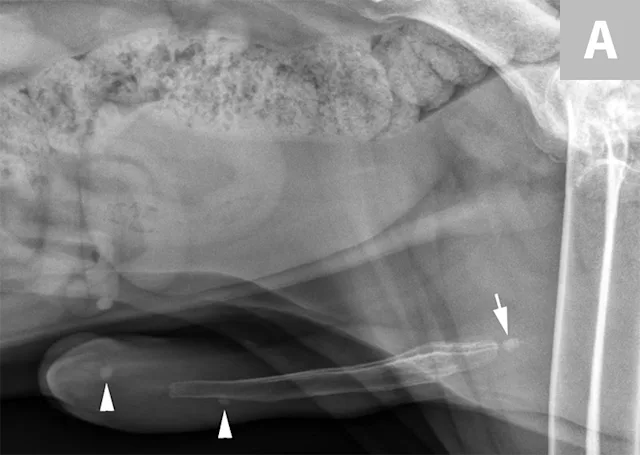

FIGURE 7A

Lateral abdominal radiograph of a cat with multiple, small, oval mineral opacities superimposed over the ventral aspect of the retroperitoneal space (arrows). These mineral opacities are arranged linearly extending from the caudal aspect of the kidneys to the level of the urinary bladder.

Differentiation between a complete vs partial ureteral obstruction can be difficult with survey radiography and ultrasonography alone. Antegrade pyelography (nephropyelocentesis with renal pelvic injection of iodinated positive contrast medium using ultrasound guidance) may be useful for documenting a complete vs partial obstruction (Figure 7).11

Antegrade pyelography is beneficial when compared with standard IV urography, as it lowers the risk of potential contrast-induced renal damage and provides excellent filling of the renal collecting system, regardless of renal function.11